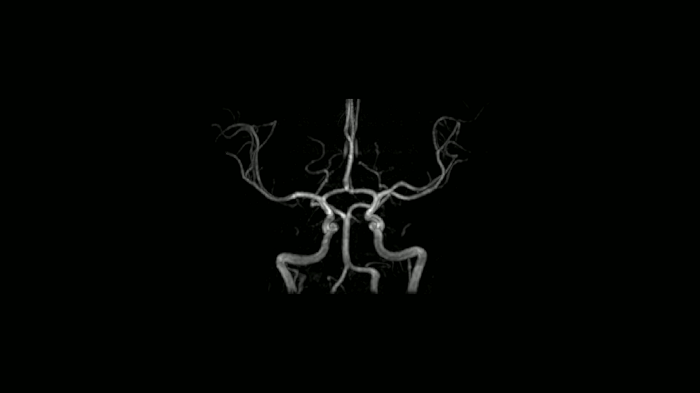

Time-of-flight angiography

Non-contrast enhanced angiography of the cranial vessels is used to detect vessel occlusions or aneurysms. High-resolution ToF angiography can also show small arteries for subtle diagnoses.

Image Courtesy: University Hospital Erlangen, Germany | Image-ID: 4aaaa0466